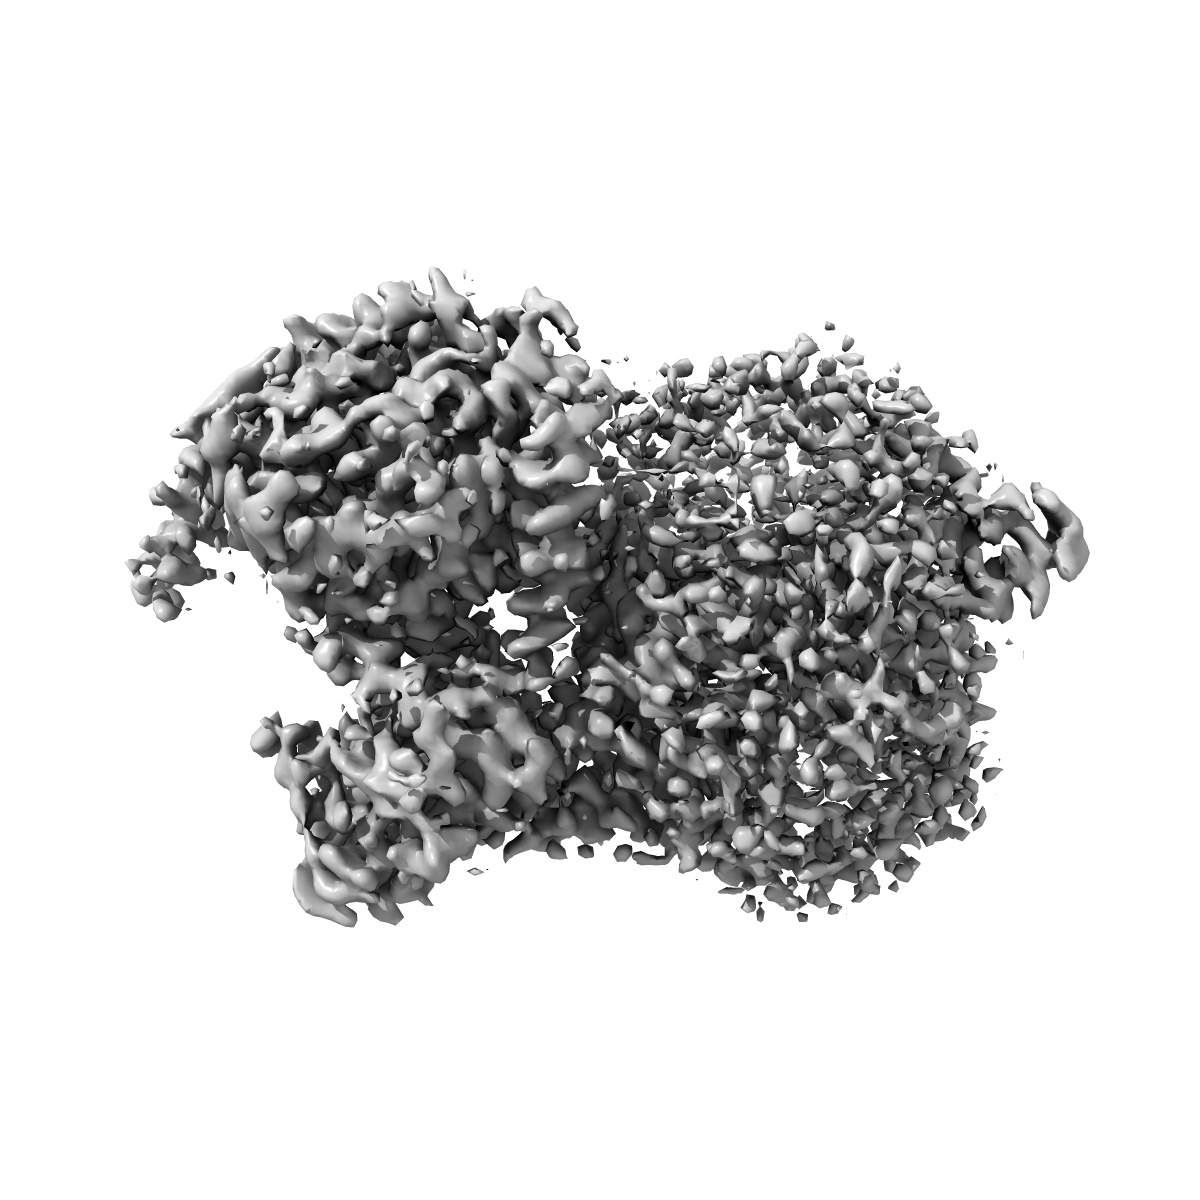

Cryo-EM structure of the human adenosine A1 receptor-Gi2-protein complex bound to its endogenous agonist

Sample: Human adenosine A1 receptor-Gi2-protein complex bound to its endogenous agonist adenosine

Structure of the adenosine-bound human adenosine A1receptor-Gicomplex.

Draper-Joyce CJ , Khoshouei M, Thal DM , Liang YL, Nguyen ATN , Furness SGB , Venugopal H , Baltos JA, Plitzko JM , Danev R, Baumeister W, May LT , Wootten D , Sexton PM , Glukhova A , Christopoulos A

(2018) Nature , 558 , 559 - 563